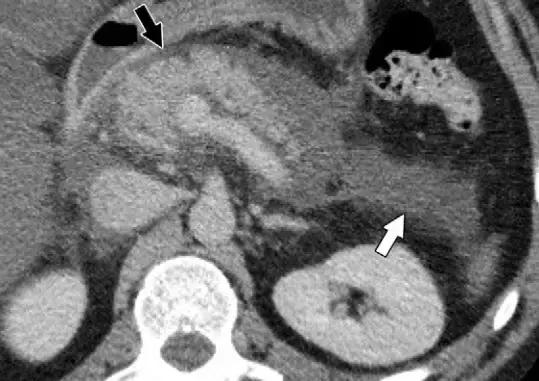

* 特别需要注意的是,胰周可有液性密度,但不会有坏死物质(图 2)。

图 2 一名 43 岁男性 IEP 患者。轴位增强 CT 图像显示胰周炎症(黑箭头)和左肾前间隙积液(白箭头),诊断为 APFC